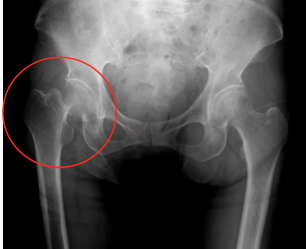

股関節周囲の骨折

高齢者人口の増加に伴い、骨粗鬆 症関連骨折である股関節周囲の骨折(大腿骨頚部・大腿骨転子部骨折(図1))は増加 の一途をたどっています。本骨折は寝たきりの原因となるばかりではなく受傷後の生命予後を確実に短縮させるため大きな社会問題となっています。これらの骨折に対して当科では全身状態のチェック後に比較的早期に手術を行っております(年間200例前後/年)。

図1-1

大腿骨頸部骨折

図1-2

大腿骨転子部骨折

図1-1

大腿骨頸部骨折

図1-2

大腿骨転子部骨折